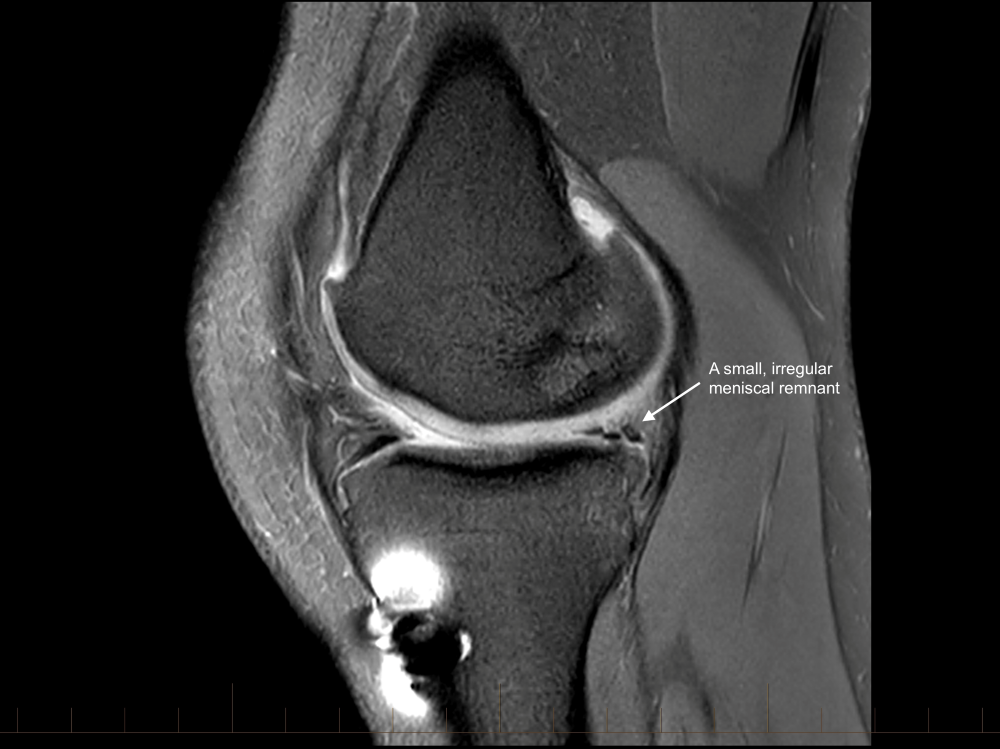

The ACL graft is ruptured with a loss of the normal ACL contour and signal. There is a focal are of full-thickness cartilage loss on the posterior, weight-bearing portion of the lateral femoral condyle. This measure approximately 15 x 10mm. There is also thinning and irregularity of the articular cartilage involving the posterior aspect of the lateral tibial plateau with a small area of full thickness cartilage loss and subchondral reactive change. These chondral changes were not present at the time of her first surgery. There appears to have been trimming of the mid and posterior thirds of both menisci. These meniscal remnants are small and irregular.